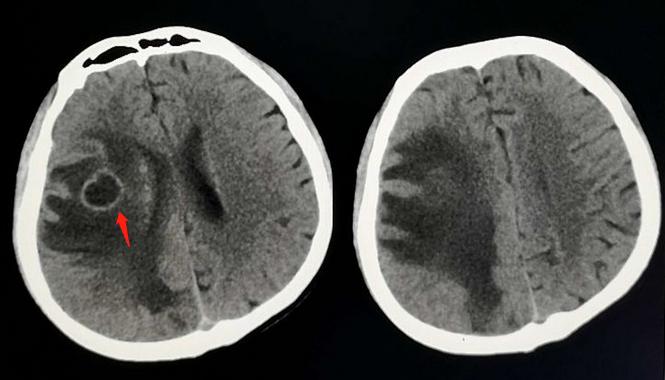

一位22岁的小伙子,走路没力气,无缘无故摔跟头,神经内科医生领着过来做了颅脑CT:

CT显示大脑半球皮质下多发环形病灶,周围大量低密度水肿带,如果是成年人,这个形态要想到转移瘤。

但病人是年轻小伙子,首先考虑脑结核瘤。